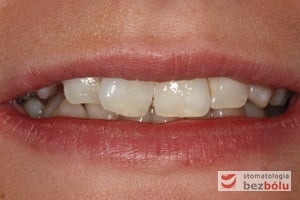

Pacjentka lat 22 zgłosiła się do naszej placówki celem podjęcia leczenia ortodontycznego. Głównym oczekiwaniem pacjentki była poprawa estetyki uśmiechu oraz brak ekstrakcji zębów na drodze do jej uzyskania. Ze względu na liczne stłoczenia zębów w górnym i dolnym łuku, dość duży materiał zębowy w porównaniu z bazą kostną, a także zgryz przewieszony boczny prawostronny po dokładnej analizie cefalometrycznej oraz analizie modeli diagnostycznych zastosowano leczenie bezekstrakcyjne z wykorzystaniem strippingu jako alternatywy dla usuwania zębów, mającego na celu uzyskanie miejsca w łuku na uszeregowanie zębów. Po fazie aktywnego leczenia trwającego 18 miesięcy zastosowano leczenie retencyjne w postaci szyny retencyjnej w łuku górnym oraz retainera stałego w łuku zębowym dolnym klejonego od kła do kła.